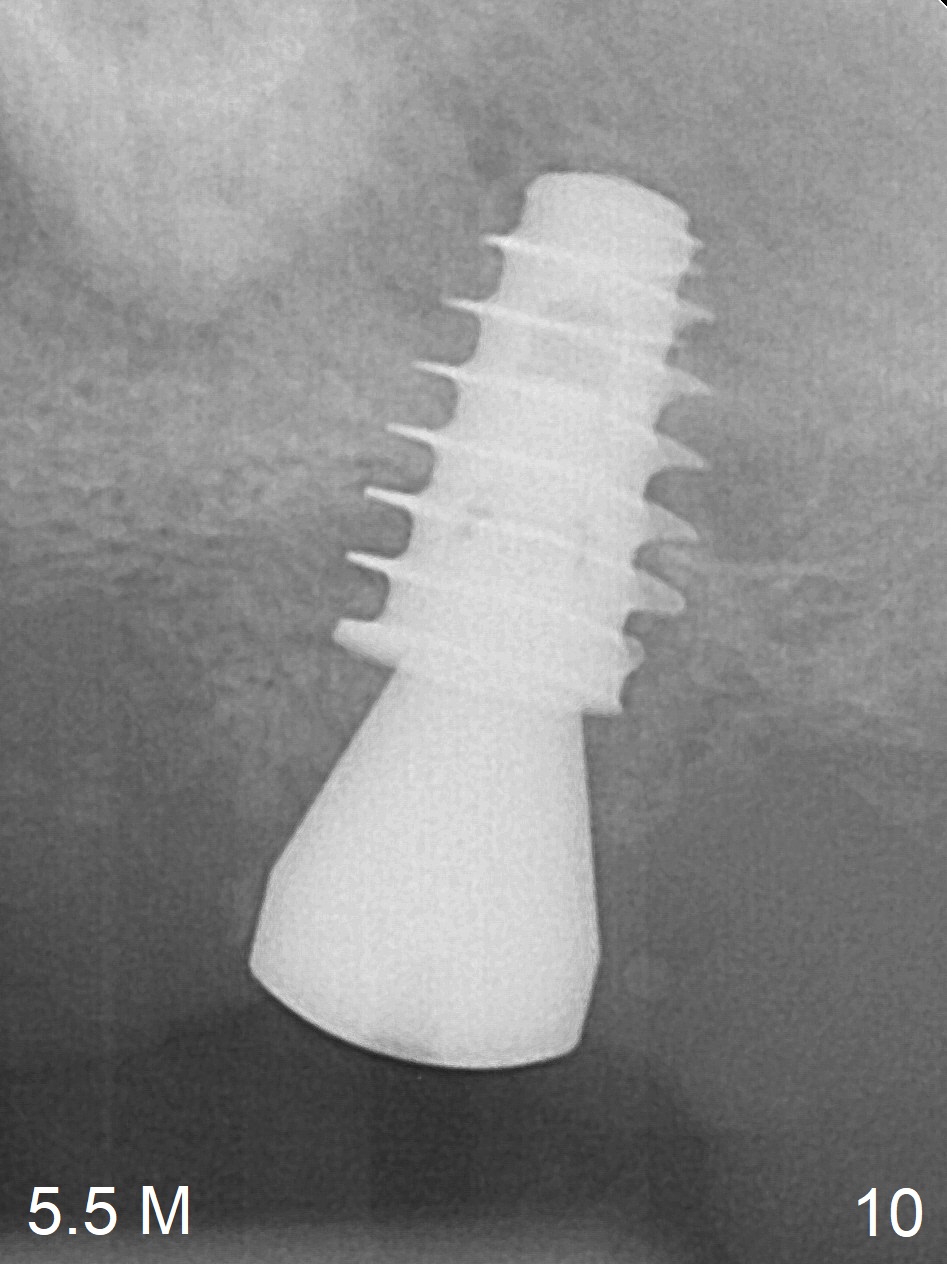

One month later, bone graft is placed mesiopalatal to the implant at #15 (Fig.7 *,8) while a 3.8x13 mm implant is placed at #13 following bone expansion (using Magic Split and Magic Expander 3.0 mm (abutment 5.5x4(5) mm). Another month later, the tooth #16 is extracted to create space for #15 restoration. Two weeks later the abutment at #15 is found to be unstable (2.5 months postop). Local oral hygiene is poor. The abutment is removed and a 6x4 mm healing abutment is placed with mild tenderness. It appears that the limited bone height is associated with low stability with CMC. Three months later (5.5 months postop), the implant seems to be stable (Fig.9,10). The implant remains stable clinically 7 months postop (Fig.11). The bone graft appears to mature and covers the abutment with provisional 24 months postop, the bony changes is related to the thick gingiva (Fig.12 ^).